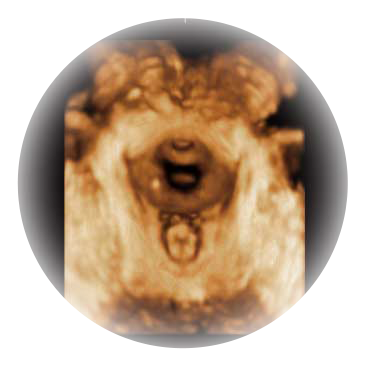

宽频带腹部凸阵探头和腹部容积探头、大角度腔内探头和腔内容积探头、独特的生殖专用曲柄探头,为妇产应用提供全面诊疗方案。

卵泡结构的自动识别和测量,可显示多组测量数据。

大角度腔内容积探头,可完整包络子宫及盆底结构,充分展示组织结构毗邻关系。